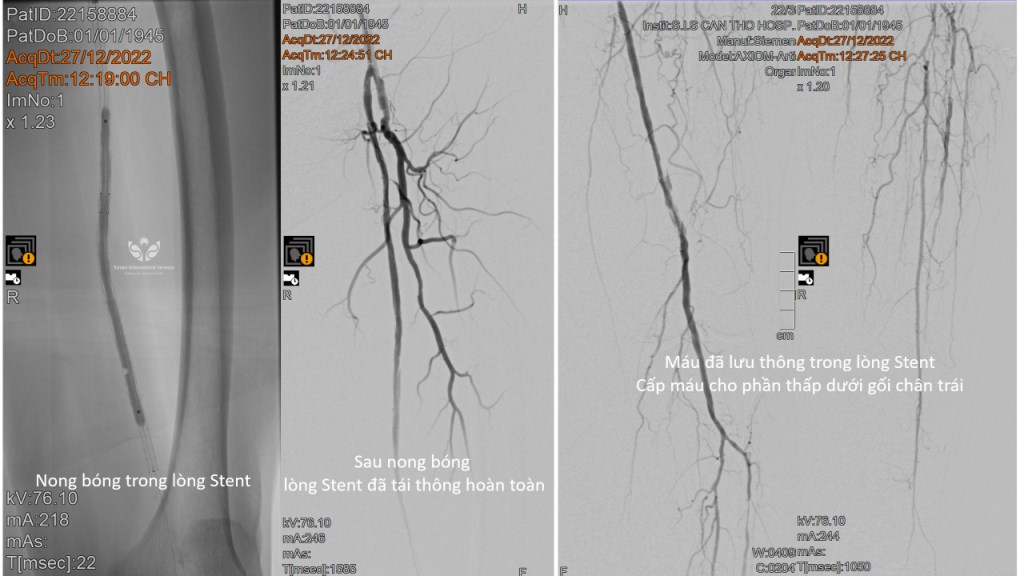

Đoạn stent 25cm bị tắc và được bác sĩ S.I.S nong bóng tái thông

Đoạn stent 25cm bị tắc và được bác sĩ S.I.S nong bóng tái thông

Sau khi nong bóng, lòng stent đã tái thông hoàn toàn, máu lưu thông đến phần thấp dưới gối chân trái

Sau khi nong bóng, lòng stent đã tái thông hoàn toàn, máu lưu thông đến phần thấp dưới gối chân trái